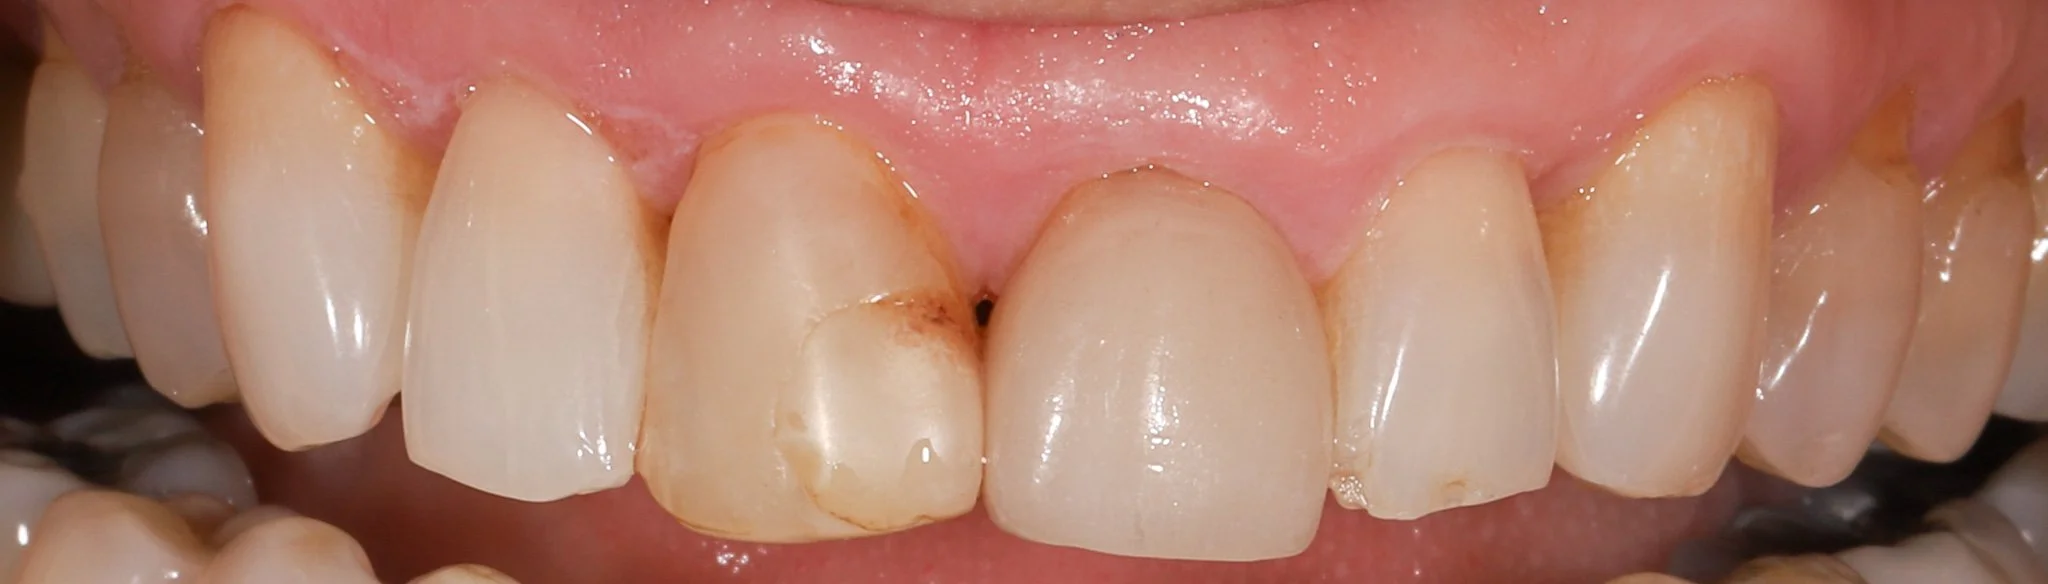

Close-up image of upper front teeth showing mismatched crowns, chipped and worn teeth with acid erosion.

Before: Heavy acid erosion, wear, poor aesthetics